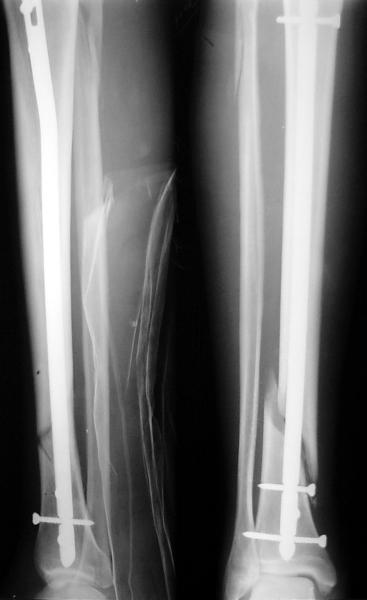

На мой взгляд, на снимках, приведённых Вами - неправильно сростающийся перелом дистальной трети большеберцовой кости, состояние после остеосинтеза интрамедуллярным гвоздём.

Как Вы пишите снимок под номером 1 - менсяц после операции, под номером 2- два месяца после операции.

Вы не послали послеоперационный снимок, поэтому трудно судить о состоянии редукции после операции.

Установка с медиальной стороны гвоздя в области дистального фрагмента дополнительного шурупа помогло бы Вам репонировать и удержать перелом в анатомическом положении, предотвратило варусную деформацию и смещение по ширине.

На мой взгляд внутрикостная фиксация переломов дистальной и проксимальной трети большеберцовой кости, за исключением поперечных, не очень хорошее решение вопроса, аппарат Илизарова или Тэйлора, позволяющие призвести закрытую анатомическую редукцию и отличное удержание отломков в период сращения.

Пример, приведённый Вами в нашей дискуссии по времени нагрузки после остеосинтеза не совсем удачный... Ваш больной имеет счастье, что первым согнулся проксимальный замыкающий винт, а не дистальный и гвоздь не пенетрировал голеностопный сустав.